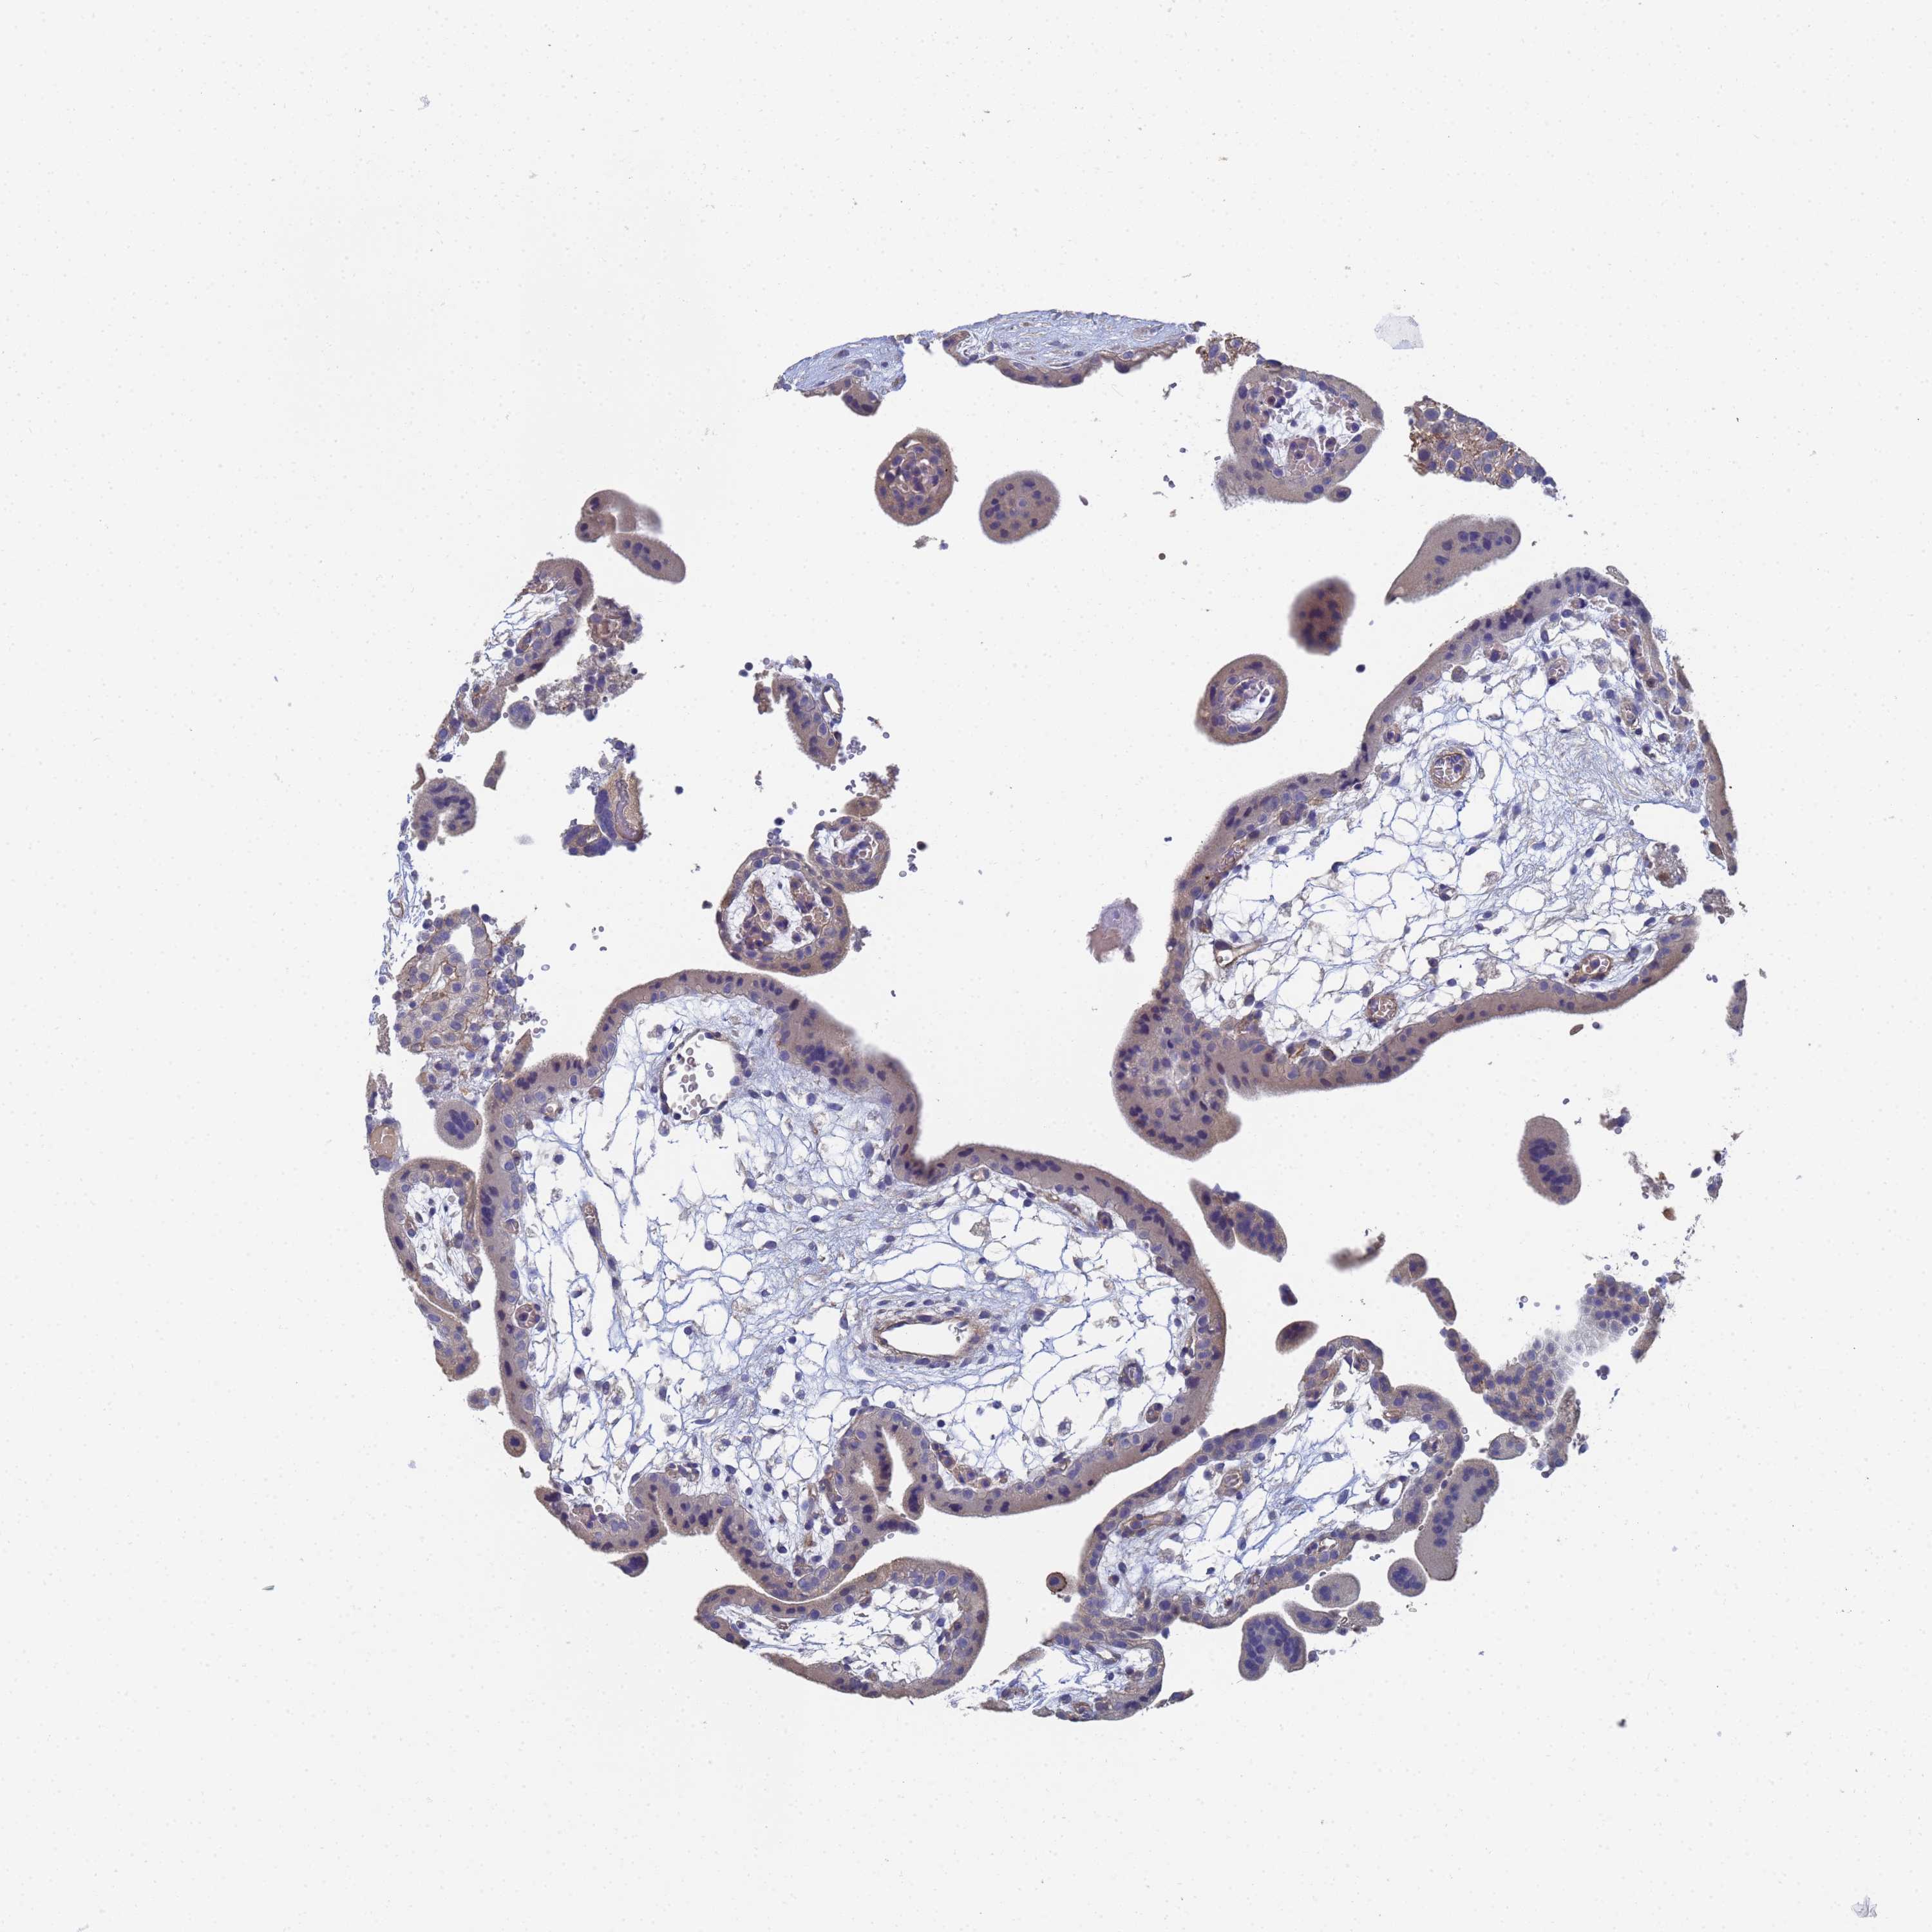

LBX2